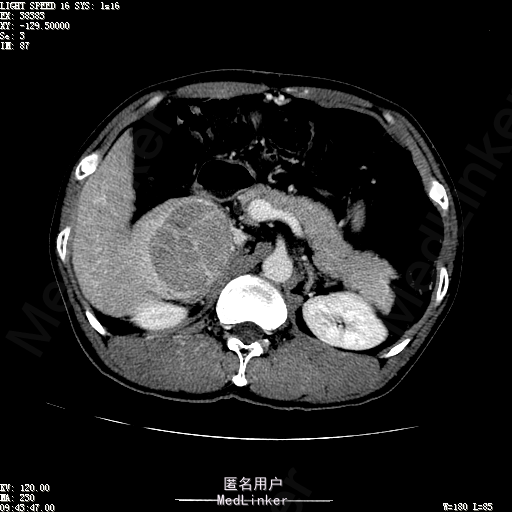

查体:体温36.4℃,脉搏76次/分,呼吸18次/分,血压110/70mmHg。神志清晰,发育正常,营养中等,体位自如,表情安静,慢性病容,检查合作。皮肤粘膜颜色正常,无瘀点、紫癜,有肝掌,无蜘蛛痣,无水肿,毛发的生长与分布正常。浅表淋巴结浅表淋巴结未触及肿大。无巩膜黄染,结膜正常。口唇红润,粘膜正常,舌正常,牙龈正常,扁桃体无肿大,无咽部充血。颈部外形对称,颈静脉正常,肝颈静脉回流征阴性,气管居中。甲状腺正常,无颈部血管杂音。胸部形态正常,呼吸运动平稳规律,无呼吸困难,肋间隙正常。触诊语颤正常,无胸膜摩擦感,肺下界位于右锁骨中线第六肋间。呼吸音正常,未闻及干湿啰音,无胸膜摩擦音。无心前区隆起,心尖搏动正常,心率:76次/分,心律齐,心音正常,无杂音,无心包摩擦音。无大动脉及周围血管征,无奇脉及交替脉,无水冲脉,无枪击音,腹型对称,无腹壁静脉曲张,未见胃肠型及蠕动波,无瘢痕,脐部正常。无压痛,无反跳痛,无腹肌紧张,无腹部包块。肝未触及,Murphy征阴性,脾未触及,肾未触及,无移动性浊音。无肝区叩击痛,无肾区叩击痛,无脾区叩击痛。肠鸣音正常4次/分,无气过水声。外阴及肛门:未查。四肢正常,关节正常,无下肢水肿,无下肢静脉曲张,无杵状指趾。 辅助检查:彩超:肝表面欠光滑,肝内占位5.2*5厘米 ct如下图

诊断:乙肝肝硬化 代偿期 原发性肝癌。 患者病史明确,目前化验转氨酶轻度升高,说明有活动性肝损伤,白蛋白降低提示肝脏合成代谢功能下降,AFP从一年前至今逐渐升高,提示活性肿瘤细胞增多。CT所见明确诊断肝癌,并有周围卫星灶,应近期行TACE治疗。 处置:DSA下肝动脉造影及TACE 手术简要经过:患者平卧位,术区皮肤消毒,铺手术巾,2%利多卡因局麻后,Seldinger法穿刺右股动脉,入血管鞘,5F猪尾管腹主动脉造影,超滑导丝yidao5F RH管腹腔干、肠系膜上动脉、左肾动脉分别造影,腹腔干造影时,见肝右叶7-8处小结节样肿瘤染色,未见外凸生长较大病灶染色。微导管超选肝右动脉注入三氧化二砷碘油混悬液10毫升,横结肠遮挡部位见较大病灶有伞状碘油沉积。复查造影未在见肿瘤染色,拔出导管和血管鞘,穿刺处压迫止血,加压包扎。术毕。

患者术后8天来,无不适,无发热,无腹痛和腹胀,无恶心呕吐,食欲睡眠好,尿便正常。 查体:神志清,巩膜无黄染,心肺听诊无异常,腹软,无压痛,肝脾肋下未触及,移动性浊音阴性,双下肢无浮肿。 复查化验结果:丙氨酸氨基转移酶 116 U/L、天门冬氨酸氨基转移酶 41 U/L、胆碱酯酶 1995 U/L↓、总蛋白 56.3 g/L、白蛋白 25.9 g/L。白细胞计数 5.8 10^9/L、红细胞计数 3.18 10^12/L、血小板计数 175.0 10^9/L、*血红蛋白 83 g/L、血小板分布宽度 15.7 、血小板压积 0.175 %、*红细胞压积 24.6 %、平均红细胞血红蛋白 26.1 pg、平均红细胞血红蛋白浓度 337.0 g/L、平均红细胞体积 77.5 fL、平均血小板体积 10.0 fL、嗜碱性粒细胞百分比 0.4 %、嗜碱性粒细胞数量 0.02 10^9/L、中性粒细胞百分比 70.4 %、中性粒细胞数量 4.10 10^9/L、嗜酸性粒细百分比 2.1 %、嗜酸性粒细胞数量 0.12 10^9/L、单核细胞百分比 12.2 %、单核细胞计数 0.7 10^9/L、淋巴细胞数量百分比 14.9 %、淋巴细胞计数 0.9 10^9/L。甲胎蛋白 23564.00 ng/mL 患者术后第8天开始行FOLFOX6化疗。CT上可见明显碘油沉积,术后甲胎蛋白下降治疗有效。嘱患者术后必须定期复查